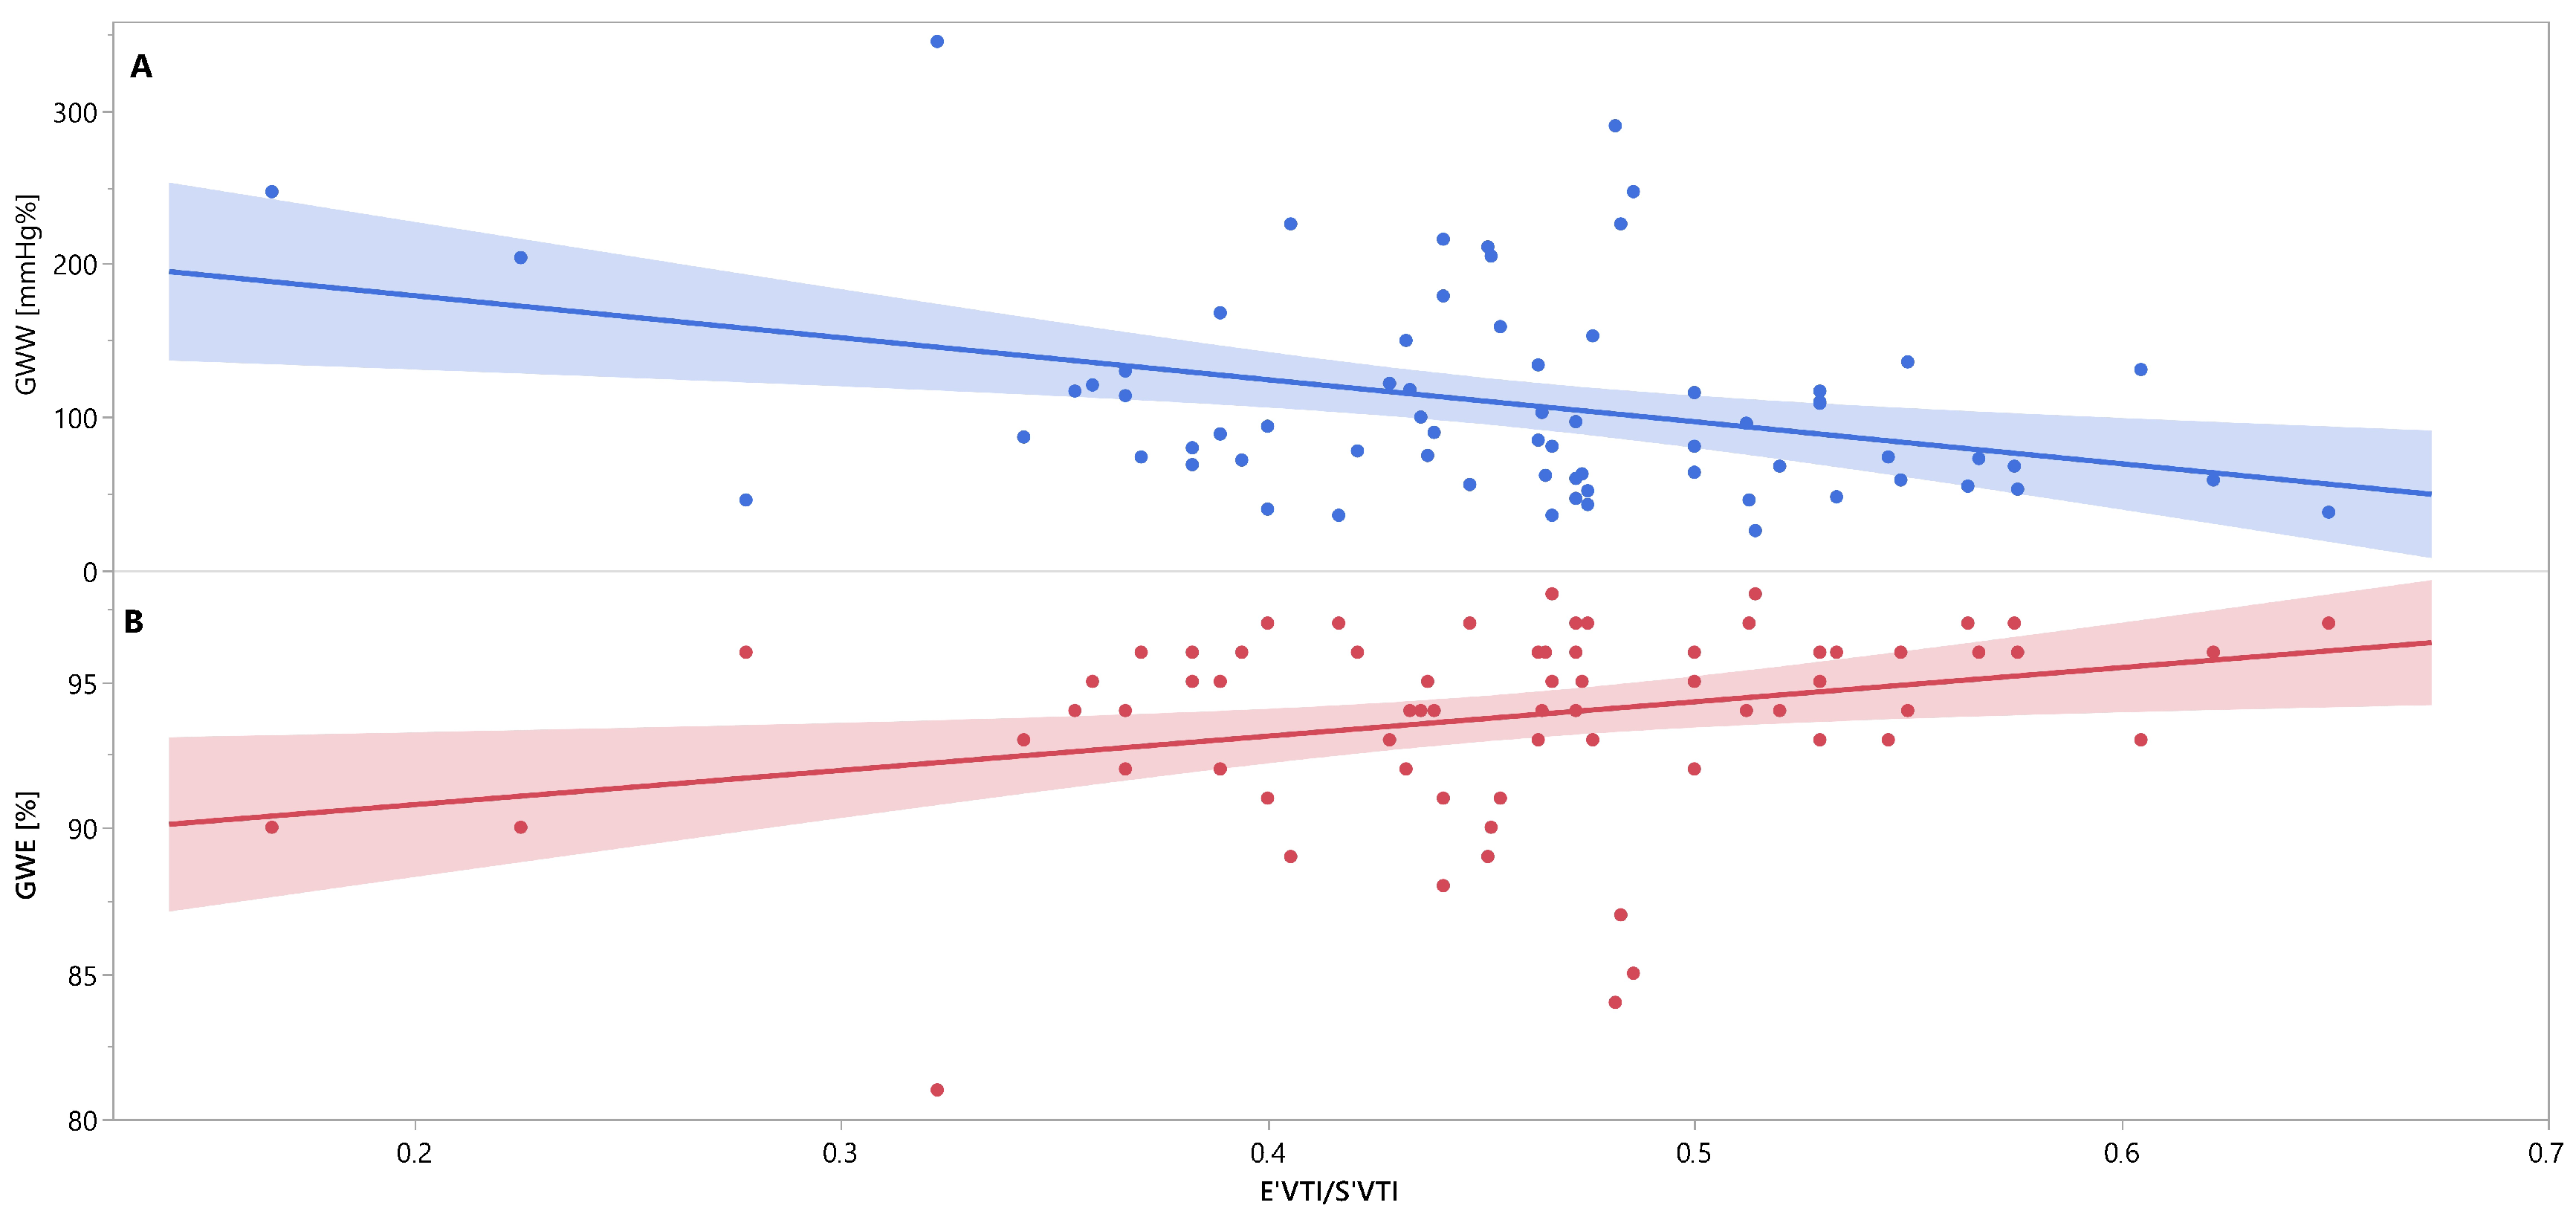

Mutual associations between PSD, GWW, GWE, IVRT and E′VTI/S′VTI are additionally shown in Figure 3, Figure 4 and Figure 5 as linear regressions.

Figure 5.

Linear regression lines for associations between E′VTI/S′VTI and GWW (panel A, line and points in blue), and GWE (panel B, line and points in red) in healthy people. Abbreviations: E′VTI/S′VTI—systolic–diastolic coupling, GWW—global wasted work, GWE—global work efficiency.